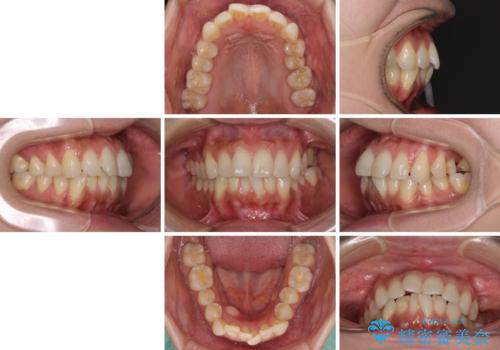

- 全体的なデコボコと、以前抜歯した歯のスペースを閉じた部分が気になるとのことで来院された患者様です。

左上第一大臼歯を抜歯した際に、スペースを閉じたそうですが、歯が傾斜してものが挟まって不快とのことでした。

インビザライン矯正で全体の歯列と整えるとともに、左上第一大臼歯部にはスペースを作り、インプラントによる補綴治療を行うこととしました。